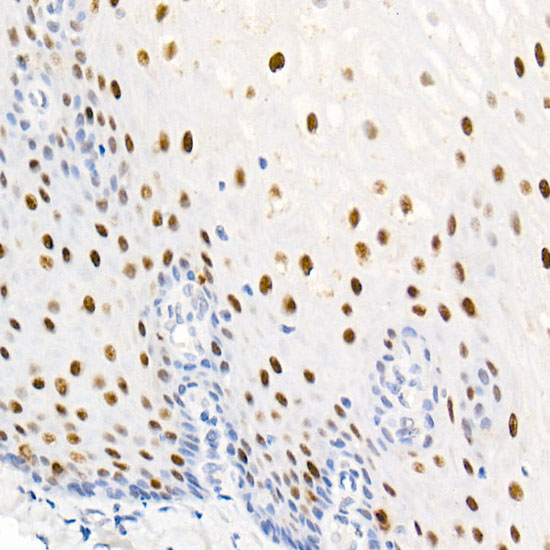

Nucleolin (NCL), a eukaryotic nucleolar phosphoprotein, is involved in the synthesis and maturation of ribosomes. It is located mainly in dense fibrillar regions of the nucleolus. Human NCL gene consists of 14 exons with 13 introns and spans approximately 11kb. The intron 11 of the NCL gene encodes a small nucleolar RNA, termed U20.

| Applications | ELISA, IHC-P |

| Antibody Type | Phosphorylated Antibody |

| Product Synonyms | Phospho-Nucleolin-T76 |

| Alternative Names | C23; Nsr1; Phospho-Nucleolin-T76 |

| Reactivity | Human |